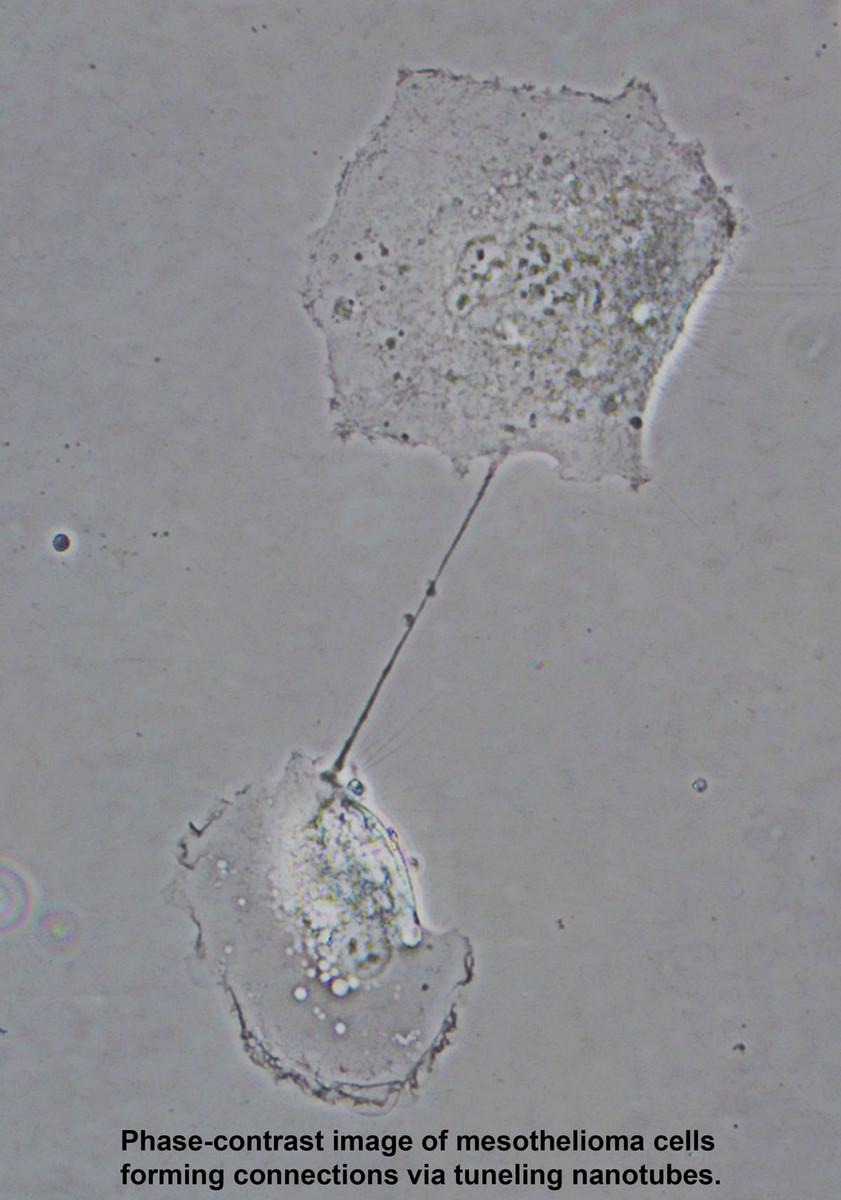

- Two Zeiss Widefield Microscopes With ApoTome (Axioplan2 Imaging Upright Stand) - Two wide-field microscopes are equipped for acquiring brightfield, darkfield, epifluorescent, phase-contrast, DIC and polarized images. Two high-resolution cameras on each microscope (one for brightfield, one for fluorescence) allow you to take the best possible images in either applications. In addition, Zeiss Apotome for structured illumination is available to take optically sectioned images.